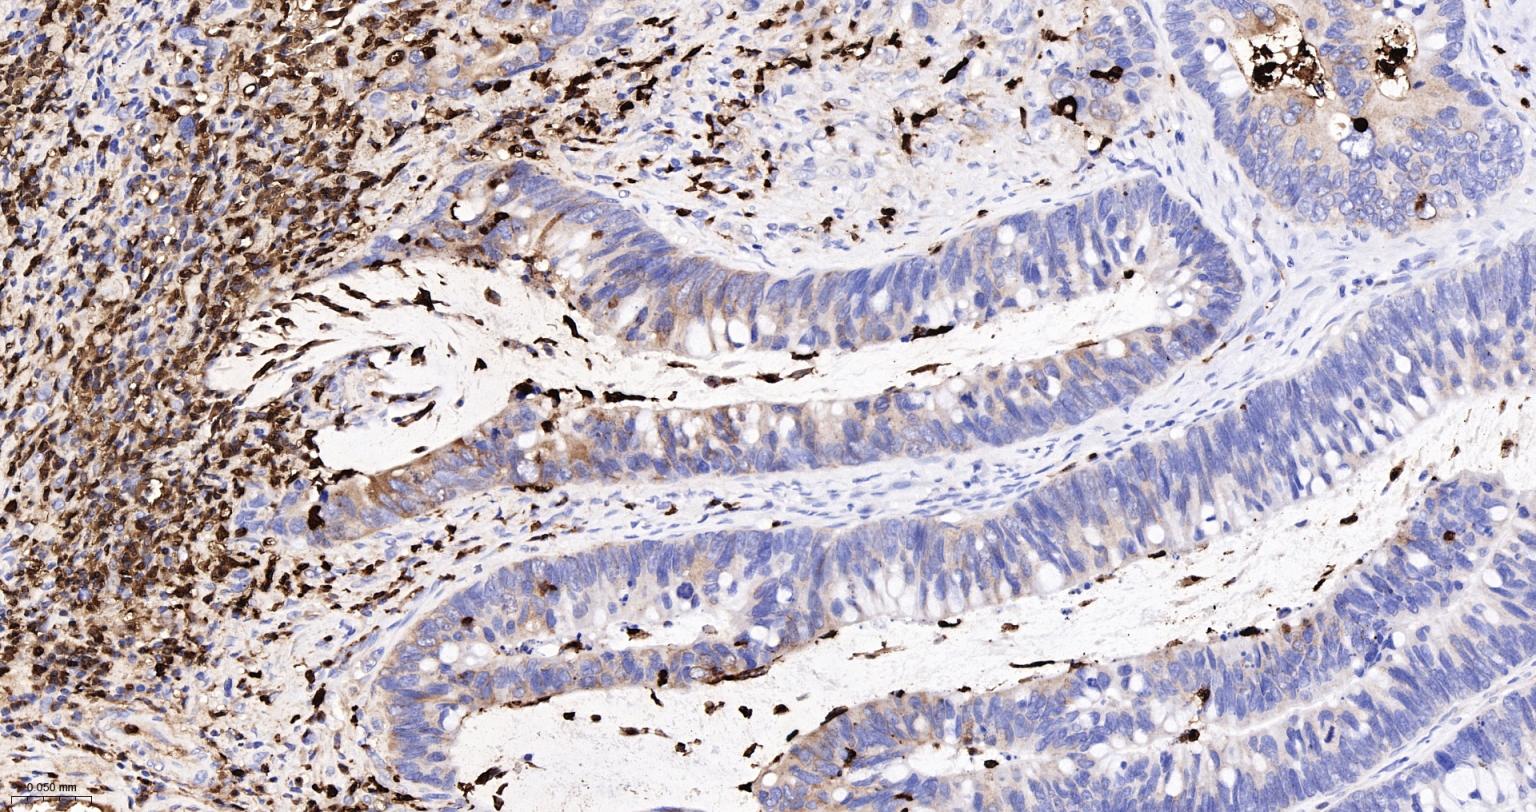

Paraformaldehyde-fixed, paraffin embedded Human Small Intestine; Antigen retrieval by boiling in sodium citrate buffer (pH6.0) for 15 min; The section was incubated with S100A8 Monoclonal Antibody, Unconjugated (bsm-61167R) at 1:200 overnight at 4°C, followed by conjugation to the bs-0295G-HRP and DAB (C-0010) staining.